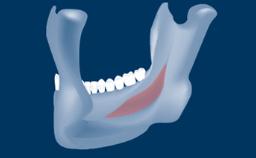

Digitally Guided Sinus Floor Elevation

In this short microlearning module on digitally guided sinus floor elevation, we delve into a specialized aspect of the digital workflow for implant-guided surgery, focusing on the use of digital guides in the sinus floor elevation technique.